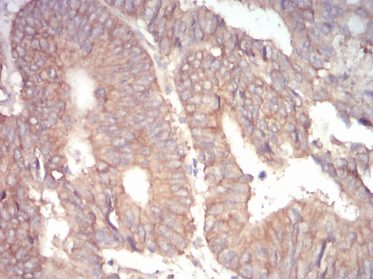

ADD1 Mouse Monoclonal antibody[5D4H1]

IHC    1/200 - 1/1000